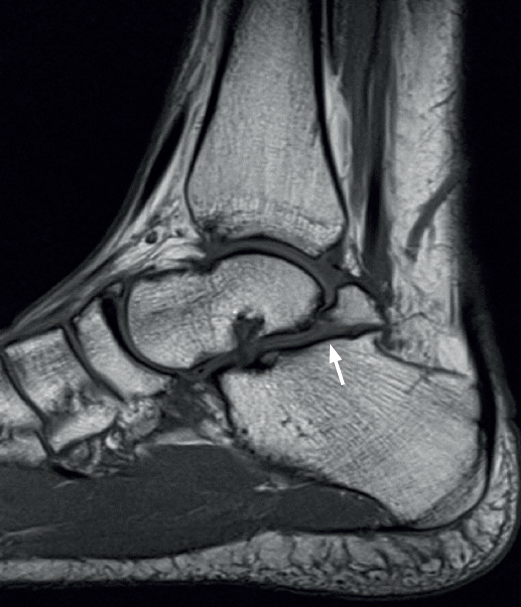

En adultos (Figuras 6 y 7), se cita como causa de pinzamiento doloroso en la cámara posterior del tobillo(50), aunque también como causa de impingement anterior(51), o confundirse con un osteocondroma a pesar de sus diferencias histológicas. Mientras el osteocondroma reproduce una arquitectura similar a la de la placa de crecimiento, la displasia epifisaria hemimélica muestra en su cubierta cartilaginosa áreas con acúmulos de condrocitos y pequeñas áreas de cartílago calcificado no reabsorbido(52). Por otra parte, la presencia de osteocondromas en la parte posterior del astrágalo es muy rara. En una serie de 7 casos en los que se produjo rotura a través del pedículo en relación con ejercicio físico, Carpintero et al. no señalan ninguna en esta localización(53).

En su evolución suele presentar dolor, grados variables de afectación articular y edema óseo visible en los estudios por RM(10) que lleva a plantear tratamientos quirúrgicos en la serie de 4 casos de Rammelt et al.(58).